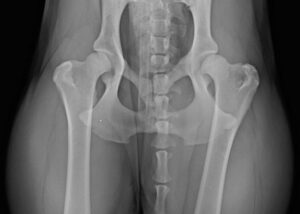

Orthopädie

Kleintierklinik, Spezielle Medizin

Orthopädie Ihr Liebling geht lahm und zeigt [...]